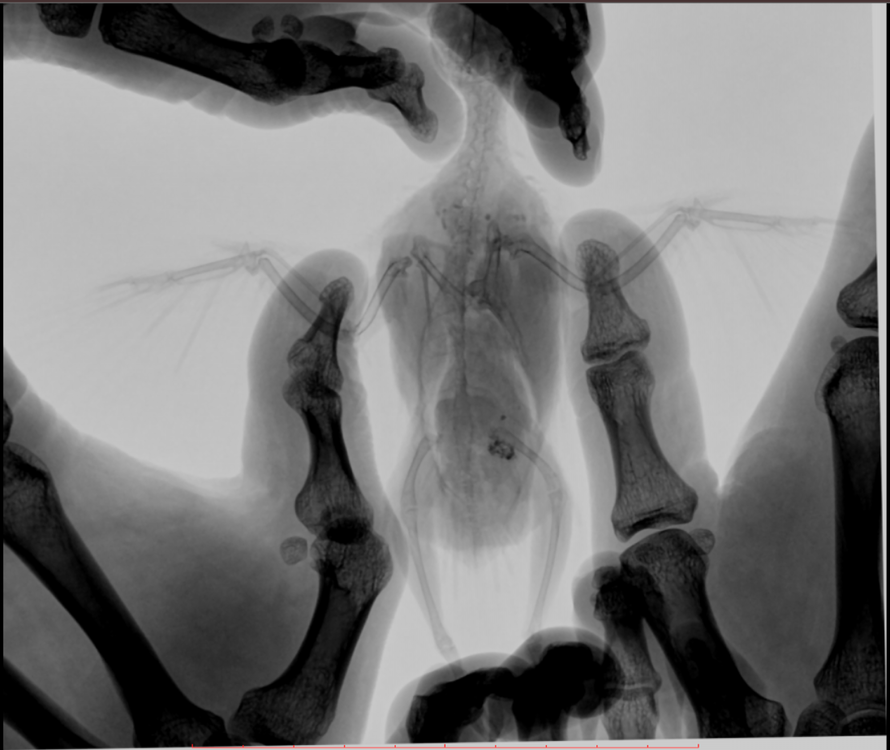

Во вторник отвозила птицу на рентген. Врач сказала, что очень сильно увеличена печень и другие органы. Также сдавлены воздухоносные мешки (из-за увеличенных внутренних органов). Отсюда - одышка. Также врач нашла перелом (старый?) ключицы. Попугая было очень сложно удерживать, поэтому снимки получились, возможно, недостаточно информативными - но какие уж получились((

@Zosia здравствуйте! Посмотрите, пожалуйста, снимки - видите ли вы на них отклонения, опухоли? Есть ли какие-то патологии? И одобряете ли вы назначенное лечение в нашей ситуации? Спасибо!

2.jpg

4.jpg

Печень видится мне увеличенной, но нужно чтобы @Zosia достоверно прочла снимки.

ответ: я увидела на снимках запущенную пневмонию, увеличенные семенники (и возможно опухоль на них), увидела в помете много палочек. Отсюда - назначение.

6.Тень семенников действительноу величена. Но снимок вами показан дурного качества. И бОльшего я сказать не могу.